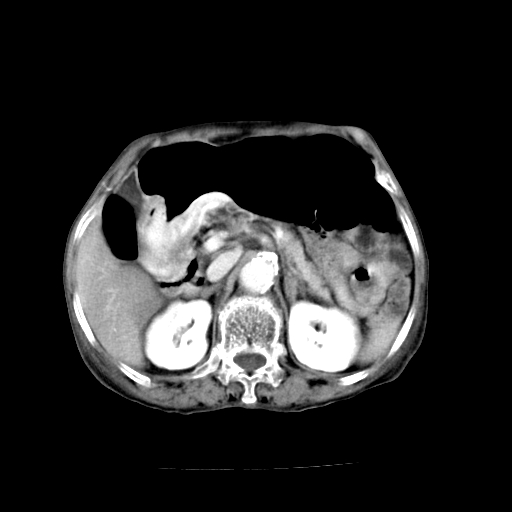

标题: CT19149:女,68岁,腹胀、恶心两周。 [打印本页]

女,68岁,腹胀、恶心两周,先做ct平扫,当时家属不同意强化,6天后家属要求增强扫描。

1、胃窦癌; 2、局灶性脂肪肝。

1)胃窦壁厚,考虑胃窦癌?建议行胃镜检查。 2)局灶性脂肪肝。

不均匀脂肪肝,胃腔改变须结合钡餐或胃镜观察